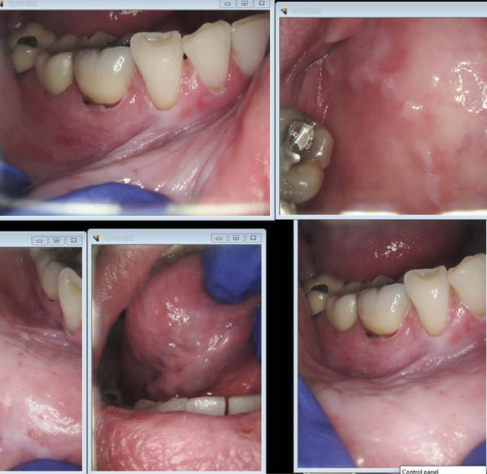

ORAL LICHEN PLANUS (OLP)

Lichenoid reaction associated with amalgam restoration

the following are clinical features of what condition?

• Autoimmune disease, unknown etiology

• Affects multiple organs

• Oral lesions resemble oral lichen planus (Not always bilateral and symmetrical)

• characteristic butterfly rash, scarring, and post inflammatory hyperpigmentation

Lupus Erythematosus